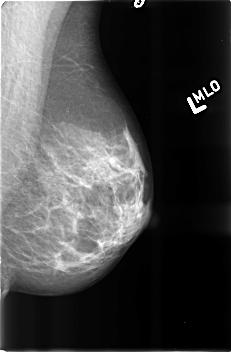

B_3360_1.LEFT_MLO

LEFT_MLO LINES 4568 PIXELS_PER_LINE 3000 BITS_PER_PIXEL 12 RESOLUTION 50 NON_OVERLAY